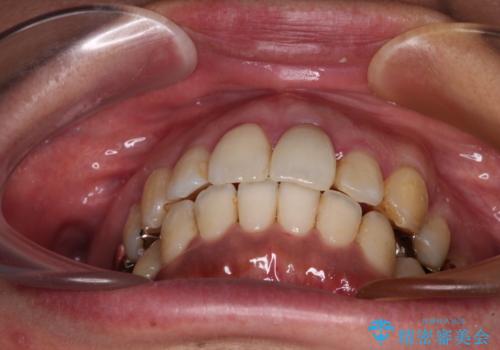

口元を引っ込めることができたため、口を閉じるときに力が入っていて皺のよっていた顎先も、スムーズに閉じられるようになったことで力がかからなくなりました。

変色して気になっていた前歯も、オールセラミッククラウンで自然な色合いにすることができました。